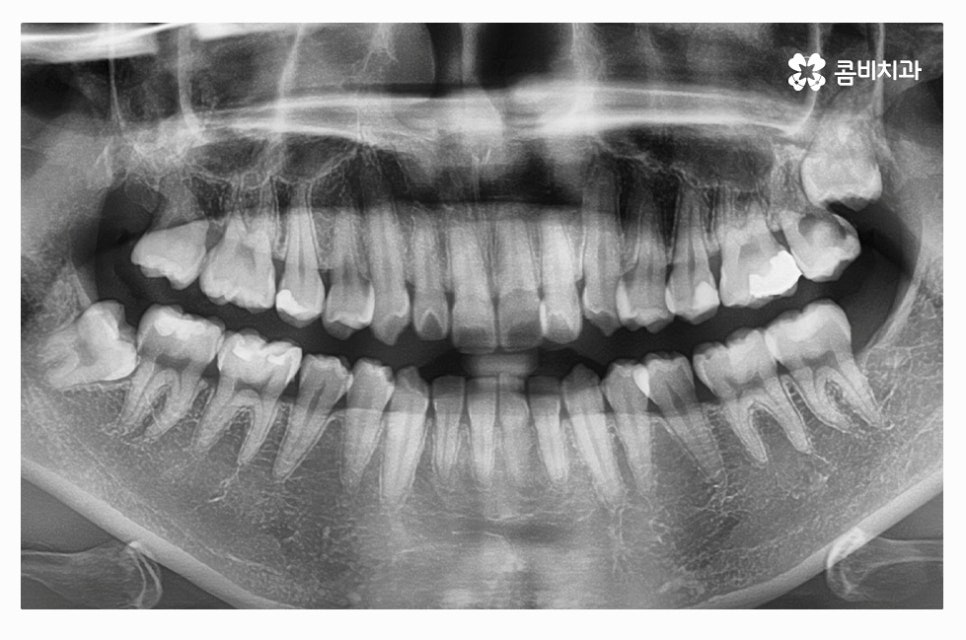

덧니교정은 치아의 이동 공간에 따라서 발치 혹은 비발치로

진행이 될 수 있는데 발치 여부는 골격, 돌출 여부, 치아의 이동 공간 확보 등에

따라서 개인차가 발생하며 치간 삭제나 악궁 확장과 같은 방법으로

비발치 교정을 하는 사례도 있어요.

발치 여부에 대해서는 정밀 검진을 통해서 의사와 상의해야 하며

무조건 비발치가 좋은 것이 아닌 심미성과 교합, 얼굴과의 조화 등을

종합적으로 파악하여 발치 여부를 정확하게 판단할 필요가 있어요.

따라서 덧니교정에 있어서 정밀검진과 구강 상태를 면밀하게

살펴보고 전문의와 충분한 상담을 하는 것이 우선이며